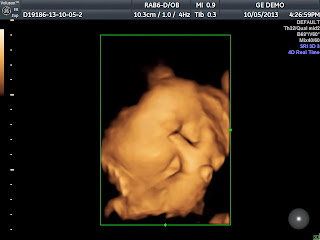

Now these machines that they had at the conference were top of the line brand new GE's that were so advanced, most sonographers had no idea how to use it. The GE representative that was there scanned me at the end so we could get a profile shot. He finally cooperated in the end and we were able to get some awesome pictures. This machine has the ability to do a typical 3D pictures, as well as what is called Real HD. It was almost scary at how realistic the images were. It was like I was looking at an actual picture of his face. It is unbelievable how far technology has come. Here are some of the amazing pictures of our beautiful baby boy!

Scary how realistic it looks, isn't it?

Its crazy how chunky those cheeks are for only being 33 weeks. We still have over a month left for him to chunk up, even more!